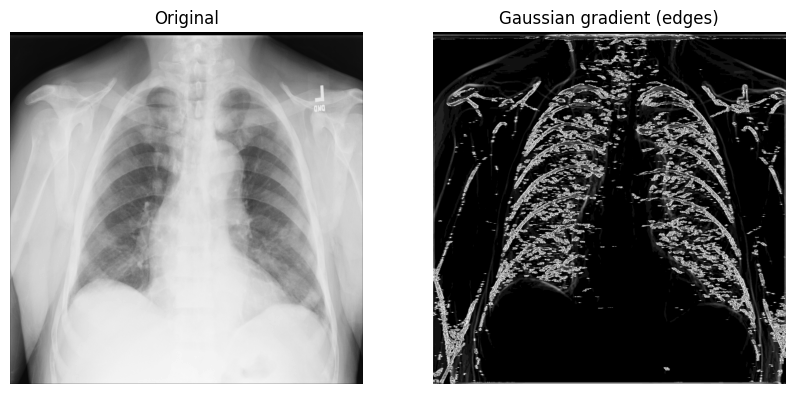

使用高斯梯度幅值法

另一种有用的边缘检测方法是 高斯(梯度)过滤器。它使用高斯导数计算多维梯度幅值,并有助于去除高频图像成分。

1. 使用带有 sigma(标量)参数的 scipy.ndimage.gaussian_gradient_magnitude() 函数(用于标准差;在下面的示例中,您将使用 2):

x_ray_image_gaussian_gradient = ndimage.gaussian_gradient_magnitude(xray_image, sigma=2)

fig, axes = plt.subplots(nrows=1, ncols=2, figsize=(10, 10))

axes[0].set_title("原始图像")

axes[0].imshow(xray_image, cmap="gray")

axes[1].set_title("高斯梯度(边缘)")

axes[1].imshow(x_ray_image_gaussian_gradient, cmap="gray")

for i in axes:

i.axis("off")

plt.show()